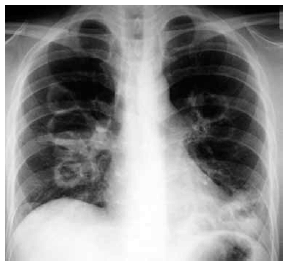

Homem de 62 anos de idade relata quadro de rinite, úlceras orais, fadiga, perda de peso e mal-estar há 3 meses. Há 1 semana evolui com tosse seca, febre baixa, rash cutâneo maculopapular e purpúrico em extremidades inferiores, com hemoptise intensa nas últimas horas, sendo internado na UTI. Exame de urina: hematúria, proteinúria e cilindros hemáticos. A radiografia de tórax realizada é mostrada a seguir.

O diagnóstico mais provável é